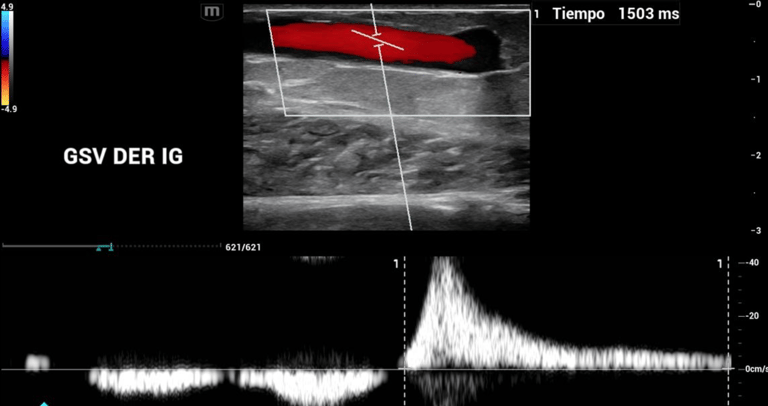

Endovascular

Intervenciones mínimamente invasivas para salud vascular óptima.